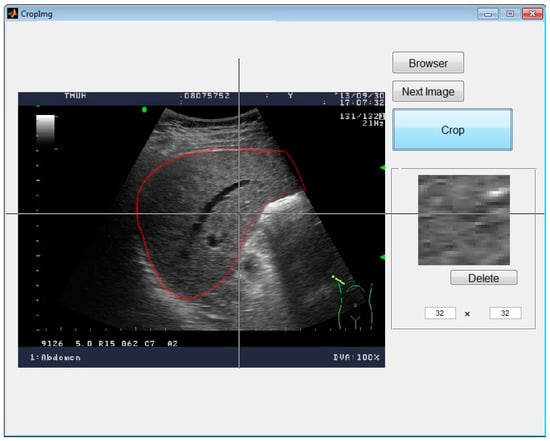

In medical imaging, the protocol of Digital Imaging and Communications in Medicine (DICOM) [12] is the standard for the communication and management of medical imaging information; therefore, DICOM files are typically used. In this research, for the convenience of image analysis, the original US images, supported by the Medical University Hospital in Taipei, were stored and then converted into 256-grayscale BMP files by MATLAB for more convenient processing. The images were from 79 cases of liver diseases including 44 cases of HCC and 35 cases of liver abscess. First, the original images were marked by experienced clinicians and verified in clinical reality. Then, the 32 × 32-pixel ROIs were selected inside the marked boundaries, as presented in Figure 1. In Figure 2, the 32 × 32-pixel ROIs were sampled from the marked image. All samples were collected from the liver disease images for later procedures, as shown in Figure 3. In this research, we sampled 400 ROIs of each kind of disease for training and testing.

Figure 2. The cropping window.